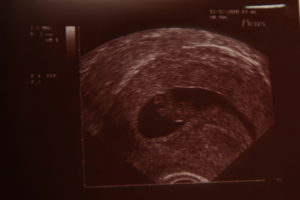

Беременность 6 недель может стать поводом для УЗИ, только если врач предполагает, что она многоплодная, либо у женщины были в анамнезе выкидыши и случаи внематочной беременности. В обычной ситуации в проведении ультразвукового обследования сейчас нет необходимости.

УЗИ обычно проводят трансвагинальным датчиком – на этом сроке данный способ более информативен. Будущая мама сможет услышать, как бьется сердечко ее малыша, увидеть его на экране монитора и на фото.

Врач делает выводы о расположении плодного яйца, его размерах и точном сроке беременности.

При обследовании может быть назначено УЗИ на 6 неделе беременности. На таком сроке УЗИ позволяет определить наличие плода в матке, то есть, исключить внематочную беременность. Можно увидеть, сколько плодных мешочков начали свое развитие в матке, то есть, выявит многоплодную беременность.

На таком сроке плод мало напоминает ребенка, эмбрион выглядит, как зернышко фасоли, да и его размер напоминает зернышко. Но зато при проведении УЗИ можно будет увидеть сердцебиение плода.

Фото плода на 6 неделе беременности

УЗИ на шестой неделе беременности помогает оценить наличие развивающейся беременности, врач использует трансвагинальный датчик из-за того, что он дает более четкие данные.

При ультразвуковом обследовании увеличивается размер матки, уже различаются отдельные части тела и органы плода. Можно прослушать сердцебиение малыша. На УЗИ до сих пор виден желточный мешок и желтое тело в яичнике.